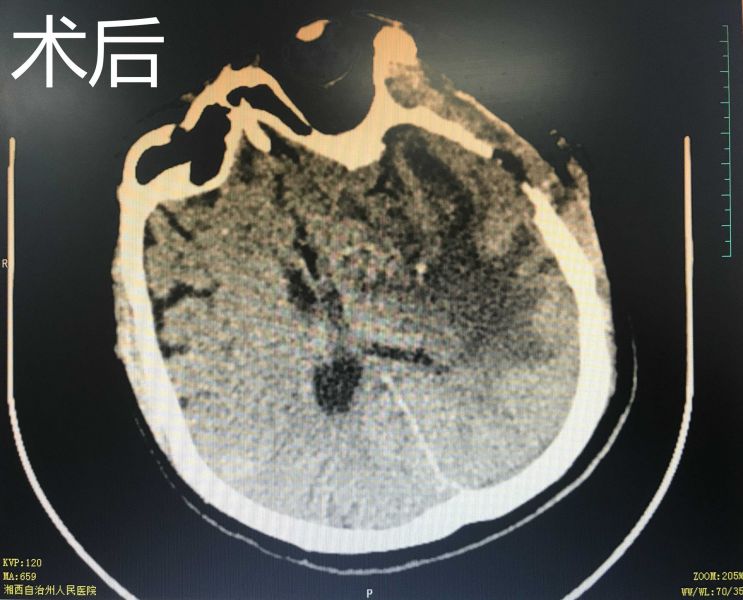

据了解,患者是一名中年男性,突发意识不清2小时入院,头颅CT检查提示:左侧基底节区出血。生死攸关之际,神经外二科主任朱英杰迅速组织术前讨论、分析病情、制定治疗方案。术前在黄纯海副院长的指导下,运用3D Slicer软件中导入CT数据并重建血肿模型,依据血肿模型制定术前计划,规划适合患者的手术路径和手术方式,并利用手机APP辅助增强现实定位技术进行精准的手术入路定位。术中田志副主任与朱英杰主任紧密协作,利用神经内镜辅助通过小骨窗微创完成脑内血肿清除术,手术切口仅4cm。次日病人复查CT颅内血肿清除干净,无残留及再次出血, 病人状态亦明显改善。

术中在神经内镜辅助下清除颅内血肿

手术切口仅4cm